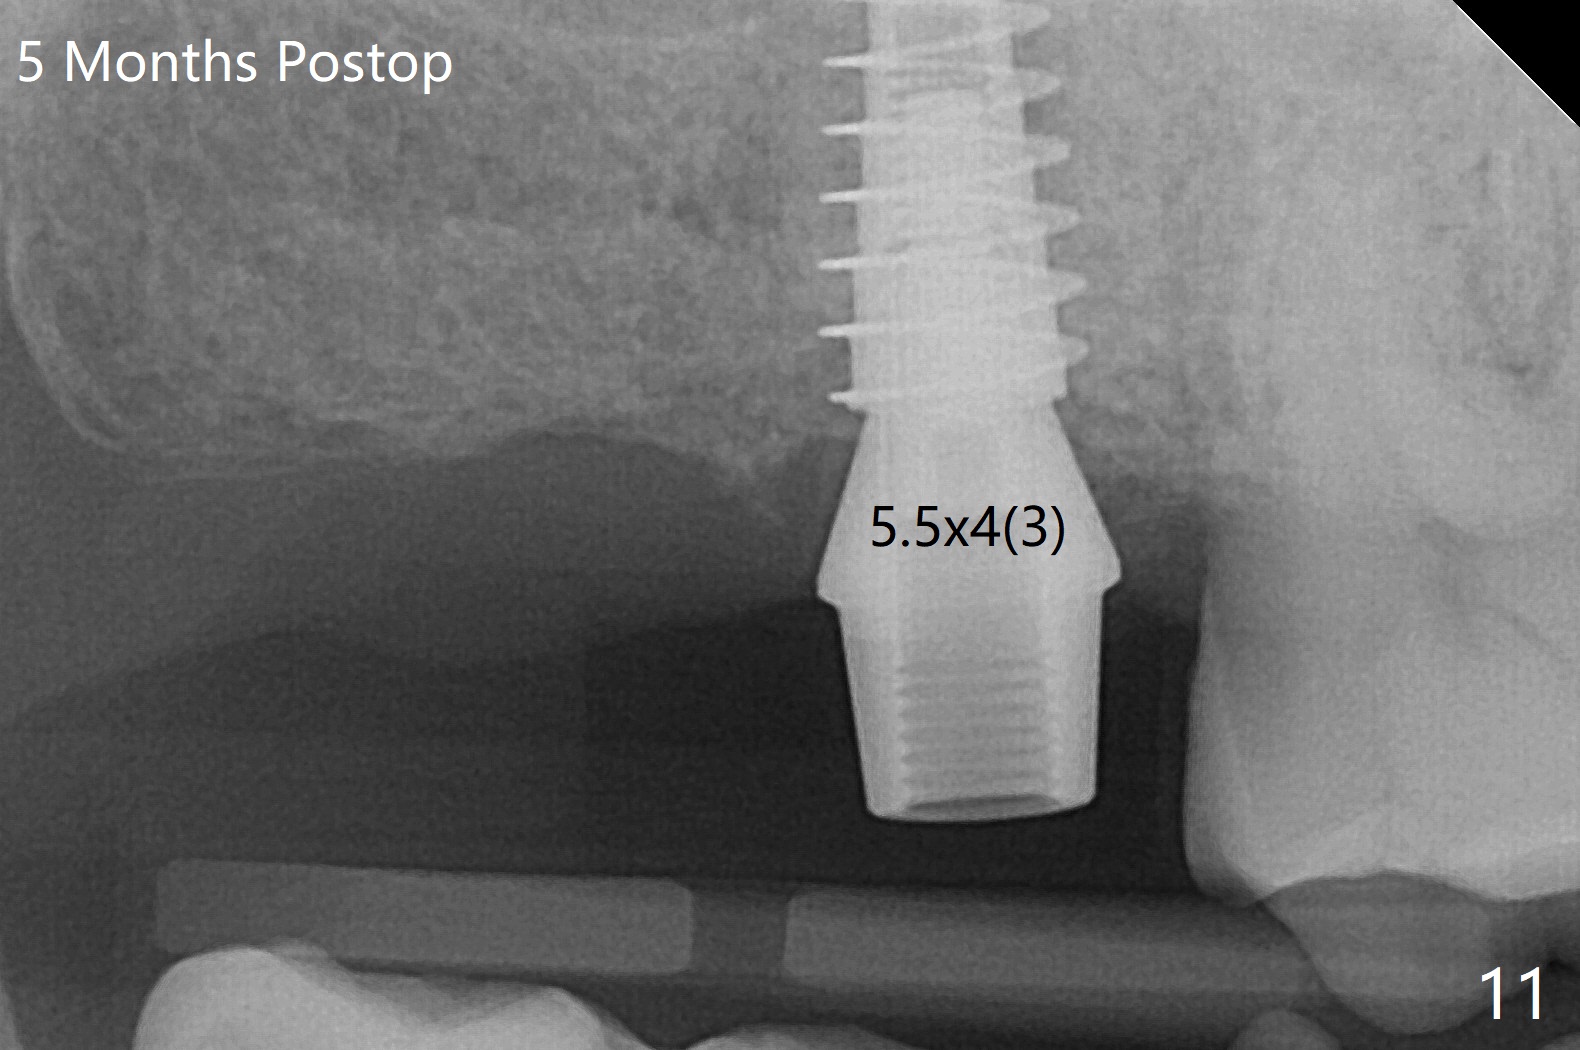

2号牙位点保存后6个月,而15号牙拔除没有植骨1-2年前(图一)。2号牙位骨质高度足够,准备不做上颌窦提升(图二),而15号牙位需要提升(图三,六)。种植术后5个月两个植体愈合均正常(图十一,十二)。